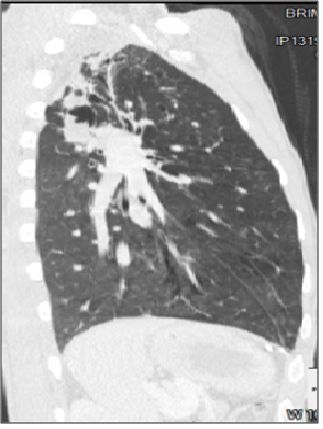

图5:矢状图显示了与支气管扩张相关的右上叶曲霉瘤。

abp在医学是什么意思如何区分4种类型的肺曲霉菌病影像学表现?_https://www.jmylbn.com_新闻资讯_第7张